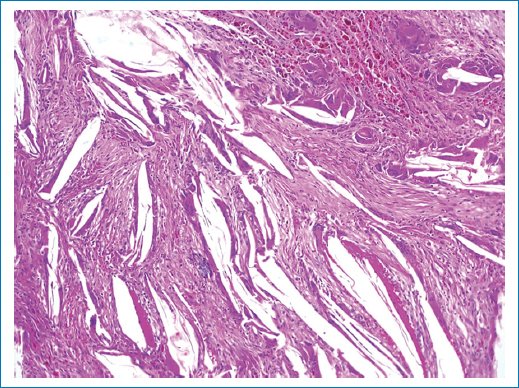

El diagnóstico histopatológico reportó un granuloma de colesterol, negativo para malignidad. Descripción microscópica: al corte histológico se identifica una lesión quística cuya pared está compuesta por tejido conectivo e infiltrado inflamatorio mixto. Se encuentra revestida por epitelio columnar ciliado pseudoestratificado con ocasionales células caliciformes. Se observan escasos focos revestidos por epitelio plano estratificado no queratinizado. Se identifican espacios elongados en el tejido, los cuales son remanentes de cristales de colesterol después de su proceso histológico. Los espacios están asociados a una reacción a cuerpo extraño, tejido de granulación y abundantes hemosiderófagos. Integrando los hallazgos microscópicos con el antecedente de cirugía, se puede establecer el diagnóstico de quiste quirúrgico ciliado y granuloma de colesterol con una posible patología primaria de quiste dentígero (Figs. 2 a 4).

Figura 2. Corte histológico en el que se identifica una lesión quística cuya pared está compuesta por tejido conectivo e infiltrado inflamatorio mixto. Se encuentra revestida por epitelio columnar ciliado pseudoestratificado con ocasionales células caliciformes.

Figura 4. Corte histológico en el que se identifican espacios elongados en el tejido, los cuales son remanentes de cristales de colesterol después de su proceso histológico. Los espacios están asociado a una reacción a cuerpo extraño, tejido de granulación y abundantes hemosiderófagos.